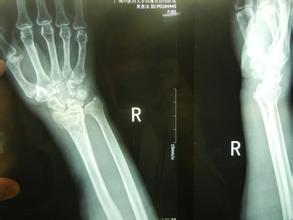

桡骨远端骨折非常常见,都有哪些原因引起的呢?

1、跌倒后腕关节处于背伸,手掌着地,重力集中于桡骨远端松质骨处而引起骨折。老年人由于骨质疏松,轻微外力即可造成骨折,大多数是粉碎骨折。这是最常见的一种桡骨远端骨折的原因。

2、跌倒后手背着地,骨折远端向掌侧及尺侧移位。这种情况比较少见。

3、跌倒后手掌或手背着地,重力向上传递后近排腕骨撞击引起桡骨关节面骨折,桡骨下端掌侧或背侧形成关节面软骨的骨折块,骨块常向近侧移位,引起腕关节脱位。青壮年发生几率高。